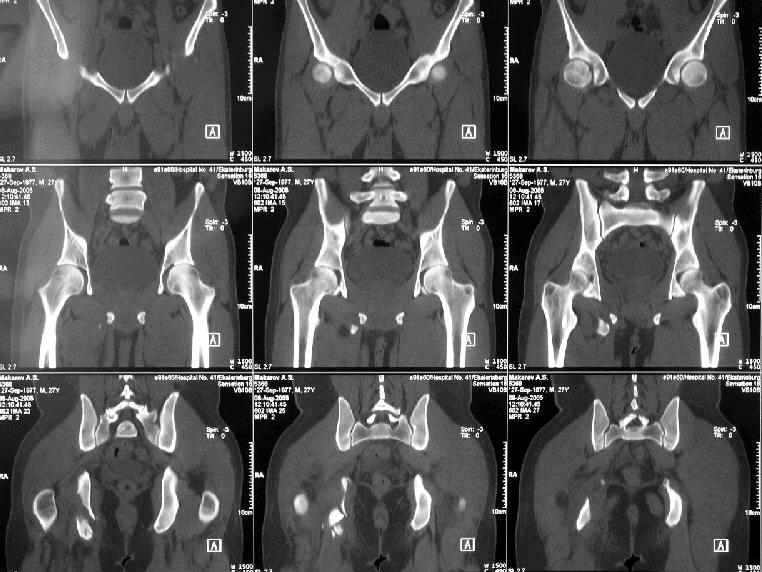

Уважаемые коллеги, хотелось бы услышать ваше мнение по тактике лечения следующего пациента: мужчина, 27 лет, получил травму на производстве 25 июня - перелом правого седалищного бугра (кт и рентгенограмма прилагаются).

Больной жалуется на боли - сидя и при ходьбе. В

настоящее время ходит, хромая, без дополнительной опоры. Оторвавшийся седалищный бугор состоит из 2-х фрагментов, один из которых раздражает седалищный нерв. Если кто-то имеет опыт оперативного лечения подобных повреждений, подскажите из какого доступа лучше это сделать. Заранее спасибо.